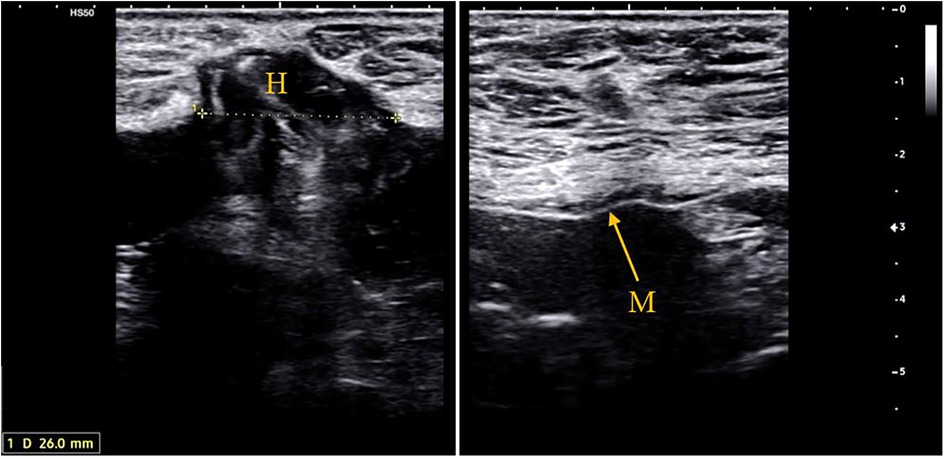

Figure 3

Axial CT scans of the pelvis demonstrating a midline incisional hernia with herniated bowel loops.

Figure 3. CT scan images at 4 years follow-up of a 71-year-old patient who underwent re-laparotomy 1 month after AAA repair for an ischemic sigmoid perforation and developed a loss of domain hernia due to a severe would infection.